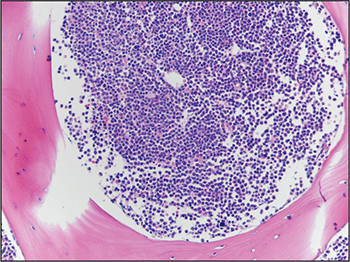

A bone marrow biopsy was then performed and revealed a hypercellular marrow with left shifted maturation in the myeloid lineage with 77 percent blasts (Fig. 6). Blast morphology was similar to the peripheral blood. Flow cytometry performed on the bone marrow was identical to the peripheral blood. Conventional karyotype performed on the bone marrow revealed a normal male chromosome complement with no abnormalities identified. Due to the clinical suspicion of APL along with blast morphology and immunophenotype, despite negative FISH and karyotype, reverse transcription-polymerase chain reaction (RT-PCR) testing was obtained.7 Testing revealed a cryptic t(15;17) with the bcr-3 transcript, and the patient was formally diagnosed with APL (Fig. 7). Despite starting ATRA, the patient developed DIC, which was effectively treated with transfusion. The patient was discharged home one month later and remains in remission more than three years later.